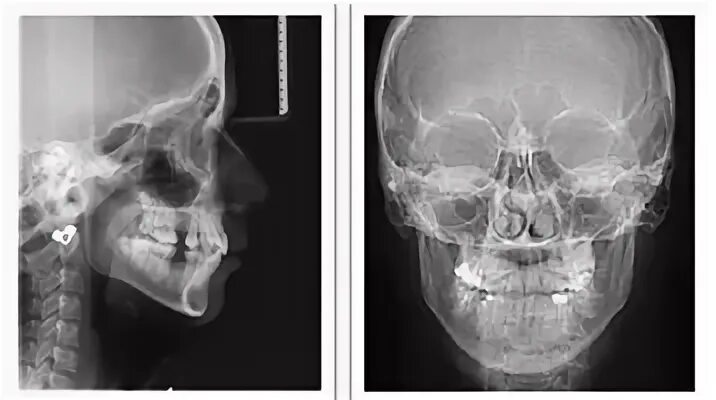

Снимок черепа в прямой проекции